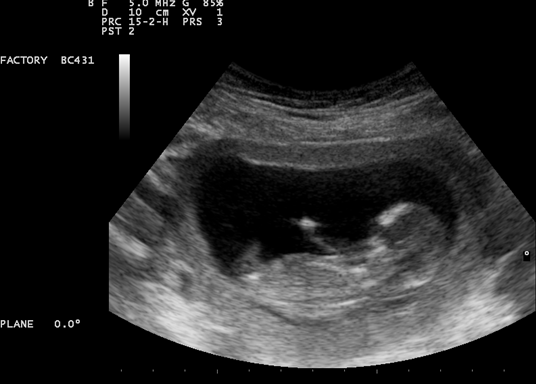

Svakom budućem roditelju posebno je iskustvo vidjeti svoju bebu na ultrazvuku, a pogotovo kad beba napravi nešto zanimljivo. Bebe u trbuhu spavaju, zijevaju, neke i sišu palac, ali jeste li vidjeli svoju bebu da radi ovakve akrobacije? Beba u ovom fascinantnom videu odbacuje se nogicama i izgleda kao da vježba u vodi!